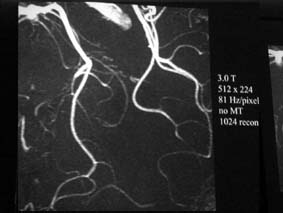

| 112: 3TのTOF MRA拡大像.ーおお,これはかなり分解能高いぞ!(片田) | 113: 1.5TのTOF MRA拡大像 |